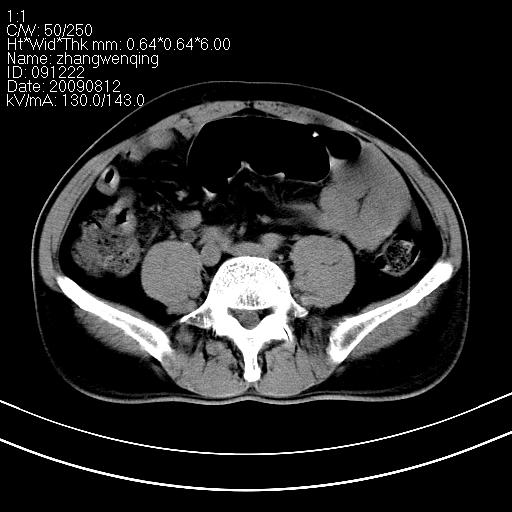

标题: CT21569:M,54Y,右侧中腹部疼痛,IVP示右侧输尿管中下段充盈缺 [打印本页]

标题: CT21569:M,54Y,右侧中腹部疼痛,IVP示右侧输尿管中下段充盈缺

右输尿管下段扩张积水。左下腹部肠管间质瘤不除外。

看不清,应打个增强,右侧输尿管扩张,右侧肠系膜上好像占位。

右侧输尿管扩张.

右侧输尿管扩张积水,考虑结石,最好做个增强除外输尿管占位性病变

右输尿管下段扩张积水,壁增厚、边缘不光整,考虑炎性改变

ct21569和ct21569b(增强)结果:阑尾腺癌,侵犯回盲部及输尿管中段。手术切除部分升结肠、回肠及受侵4cm之输尿管,做回-横结吻合,输尿管支架置放术并吻合,术后病理腺癌,阑尾来源可能性大。

右侧输尿管扩张似见软组织密度影,输尿管占位不能排除。